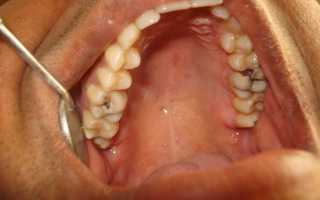

На фотографии показан осмотр зубов с помощью стоматологического зеркала с начальными стадиями кариеса.